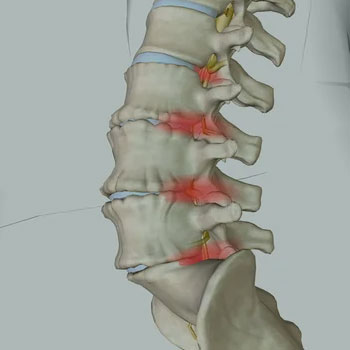

ESPONDILOLISTESE

DOR

FACETÁRIA

DOENÇA DEGENERATIVA DISCAL